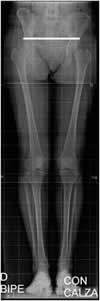

Fig 99. Longitud de extremidades.

Rx AP. La longitud de las extremidades es simétrica.

La dismetría de los miembros inferiores generalmente ocurre por acortamiento, que desencadena mecanismos compensatorios. Es común el acortamiento de pocos milímetros sin repercusión clínica y con predominio en el lado derecho. Entre 5 y 20 mm de diferencia, hay basculación de la pelvis. Mas de 20 mm ocasiona escoliosis vertebral y deformidad en rodillas y tobillos. (3). (Fig 100 y 101).

Fig 100. Desbalance pélvico.

Rx AP. Acortamiento izquierdo, con elevación de la cresta iliaca derecha. (Línea continua).

Fig 101. Desbalance pélvico.

Rx AP. Acortamiento derecho, con elevación de la cresta iliaca izquierda y escoliosis lumbar derecha.